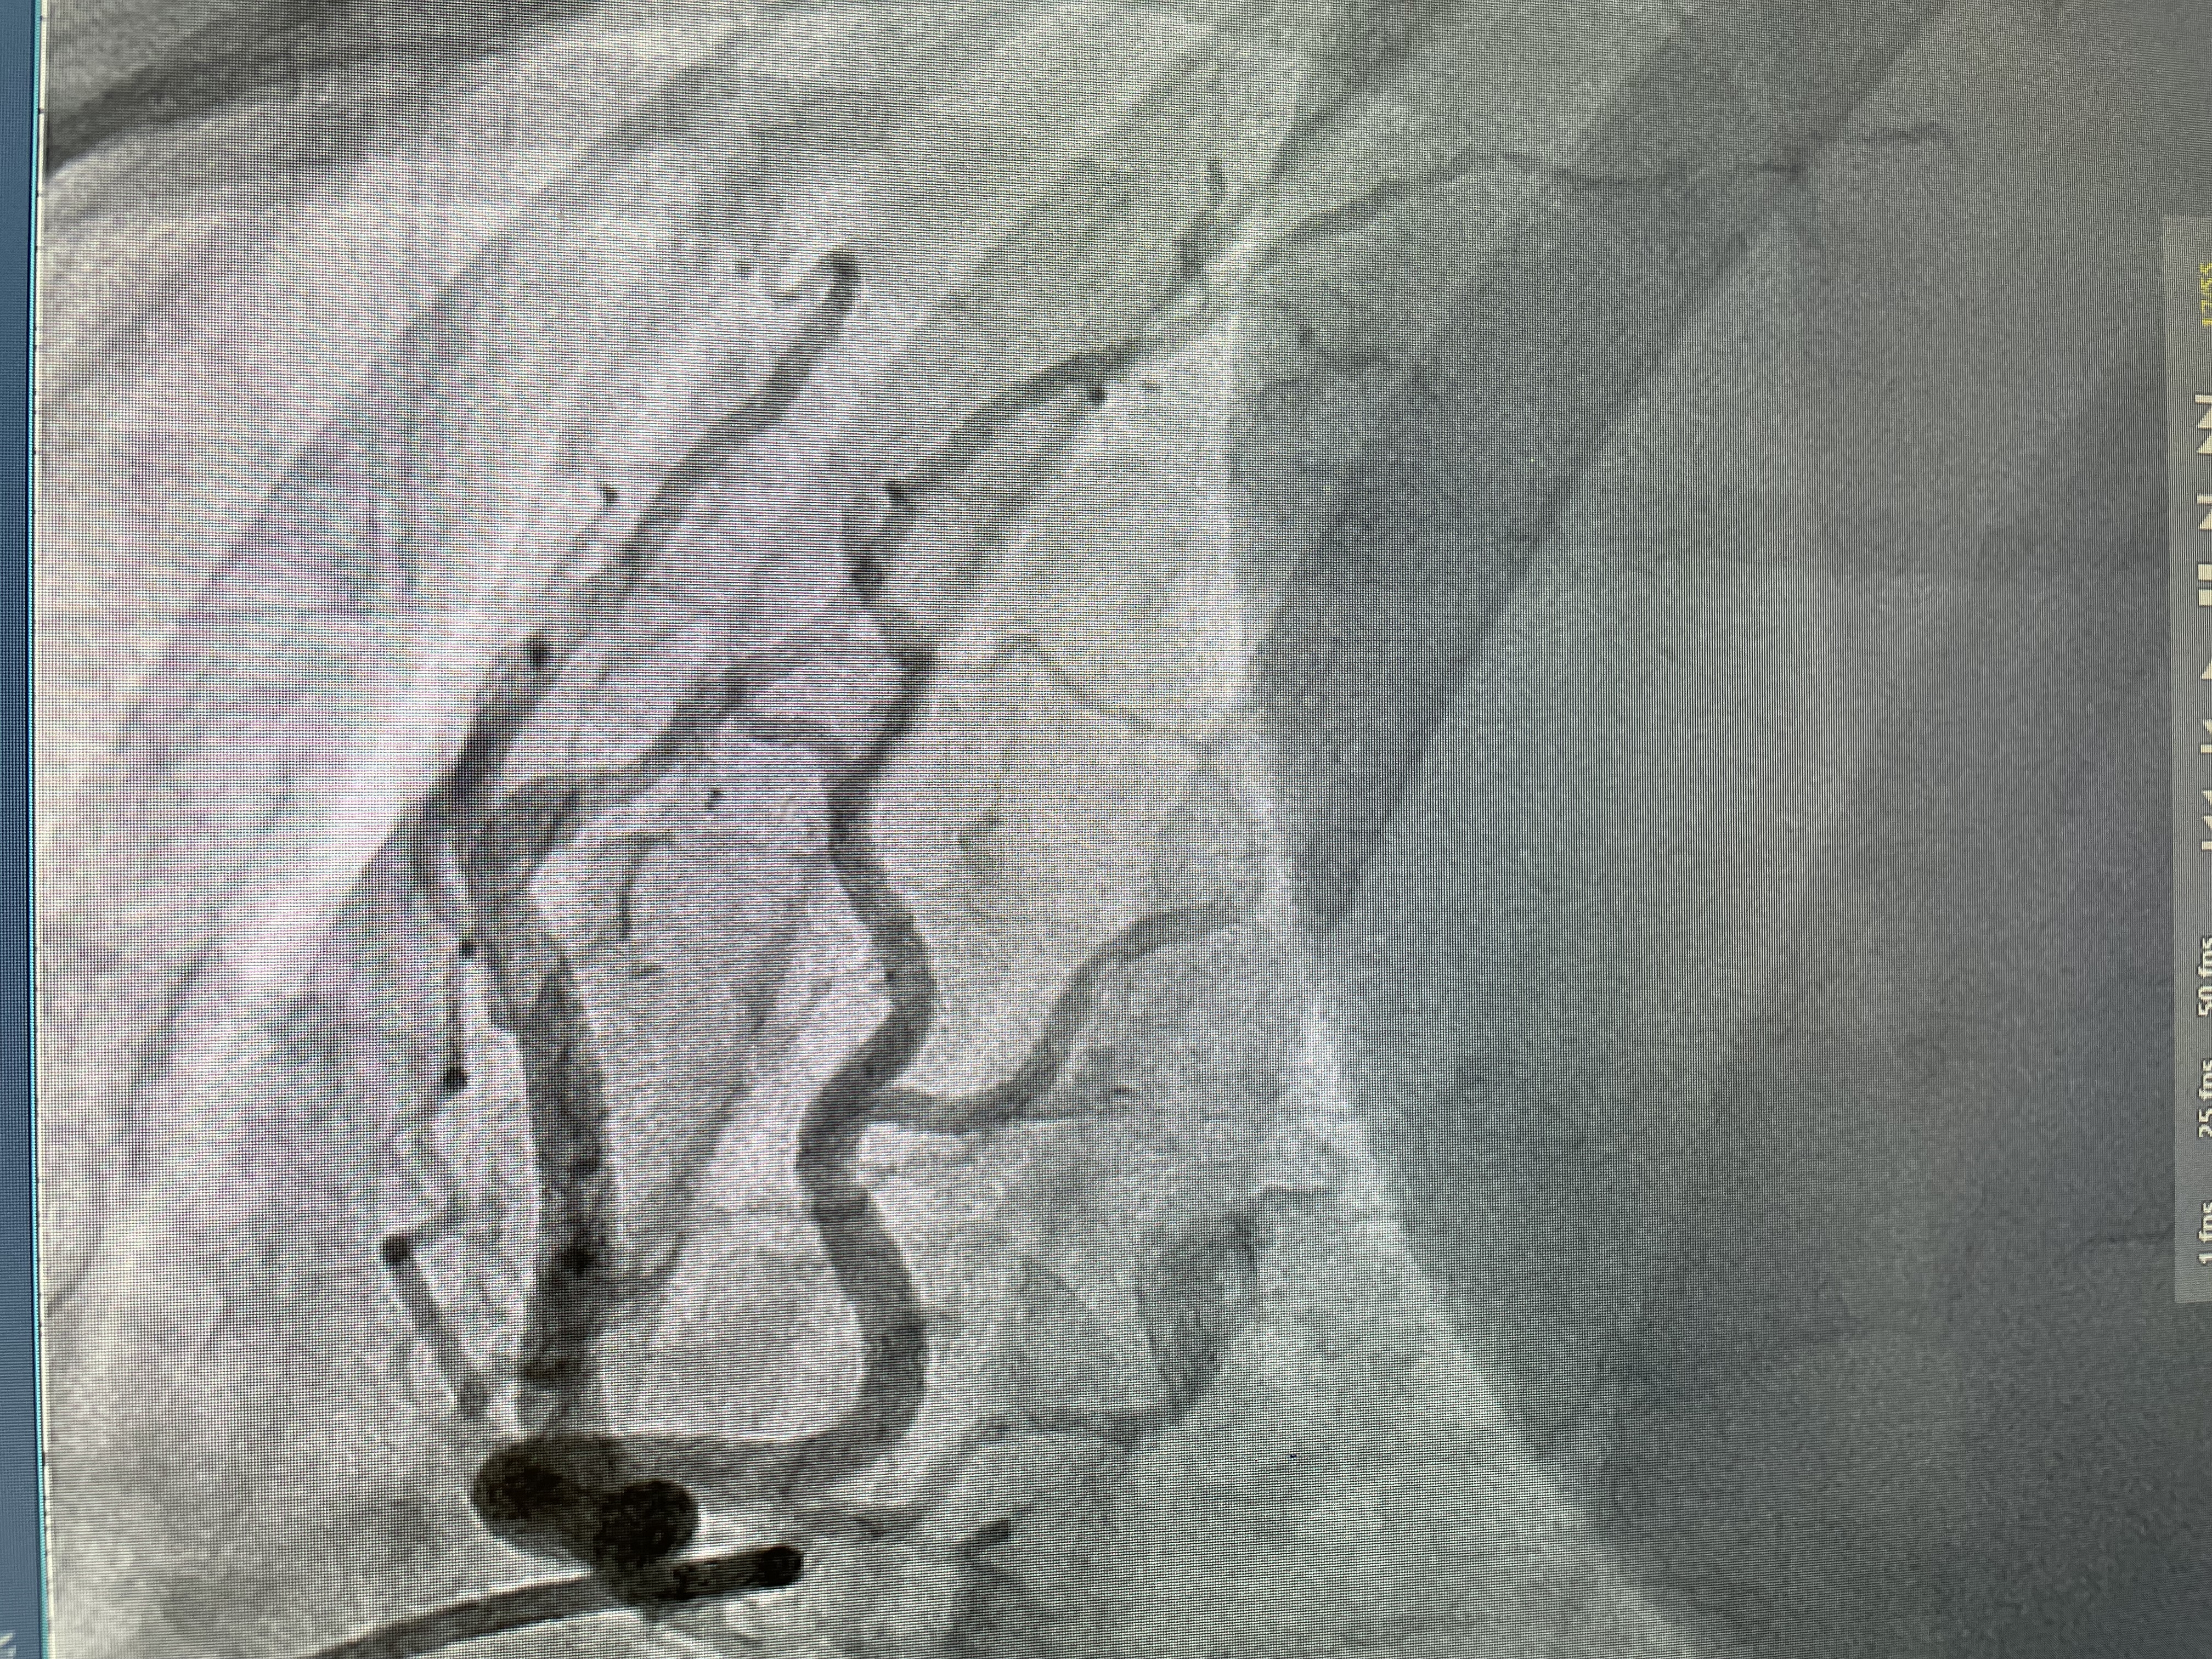

Spontaneous coronary artery dissection: Case series and review of associated cardiovascular risks

Spontaneous coronary artery dissection (SCAD) has emerged as an important cause of ACS, myocardial infarction, and sudden death particularly among young women and individuals with few conventional atherosclerotic risk factors. We reveiwed possible risk factors that could predispose to SCAD.

13 patients presented with SCAD represented % 0.5 of the total number of patients who underwent cardiac cathaterizations for chest pain requiring admissions. 11/13 (84%) were female. 5/13 (38%) were Caucasian or Hispanic, and 3/13 (23%) were African-American. Mean age age was 49.3 + years. 8/13 (61%) had associated hyperlipidemia with LDL levels > than 110 mg/dL, 9/13 (64%) had an A1c < 5.6% and only 1/13 (0.07%) had A1c of 6.4%. HTN was present in 6/13 (46%) of patients, and family history of SCD or heart disease were only seen in 2/13 (15%). None of the patients had features suggestive of associated fibromuscular dysplasia or connecive tissue disease. D-dimer was elevated in 5/13 (38%) with average value of 1578 ng/dL. Inflammatory markers were reviewed, only 3 patient has had ESR and CRP ordered, and only 1/3 had a mildly elevated CRP 3.9 mg/dL. Only 1/13 (0.07%) required intervention which was due to further drop in her ejection fraction requiring PCI, with improvement in her symptoms. All patients were treated with dual anti-platelet therapy for 1 year, 1 was discontinued due to persitent chest pain and decision was made to treat with only aspirin. Traditionally, risks for SCAD were thought to be due to non-atheresclerotic factors, however our case series shows that more then 60% of patients had elevated LDL's and 46% with hypertension, implying that traditional atheresclerotic risk factors should not be ignored and may play a crucial role. Autoimmune diseases were not found in any of our patients.

In this series patients who had SCAD had conventional risk factors of CAD including HLD and hypertension. The variability of co morbidities makes the identification of specific risk factors very difficult and none of the patients had Fibromuscular dysplasia or any signs of inflammation. Elevated D Dimer was also seen in a majority of patients, and all but one was managed medically with a favorable outcome